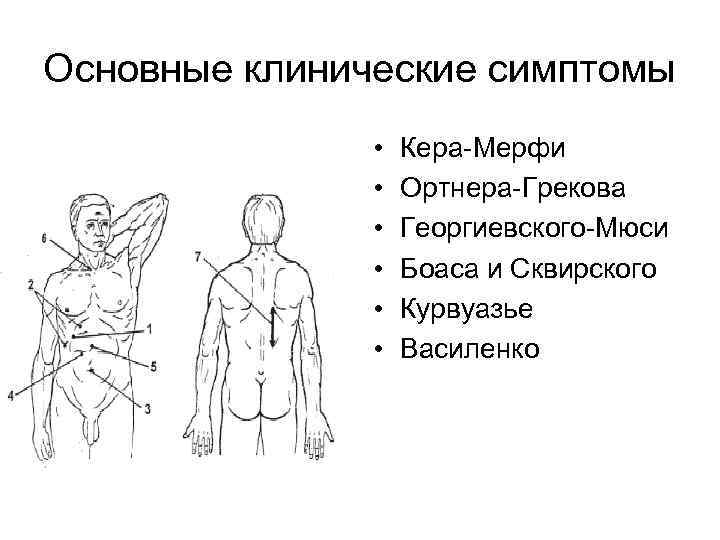

Основные клинические симптомы • • • Кера-Мерфи Ортнера-Грекова Георгиевского-Мюси Боаса и Сквирского Курвуазье Василенко

Основные клинические симптомы • • • Кера-Мерфи Ортнера-Грекова Георгиевского-Мюси Боаса и Сквирского Курвуазье Василенко